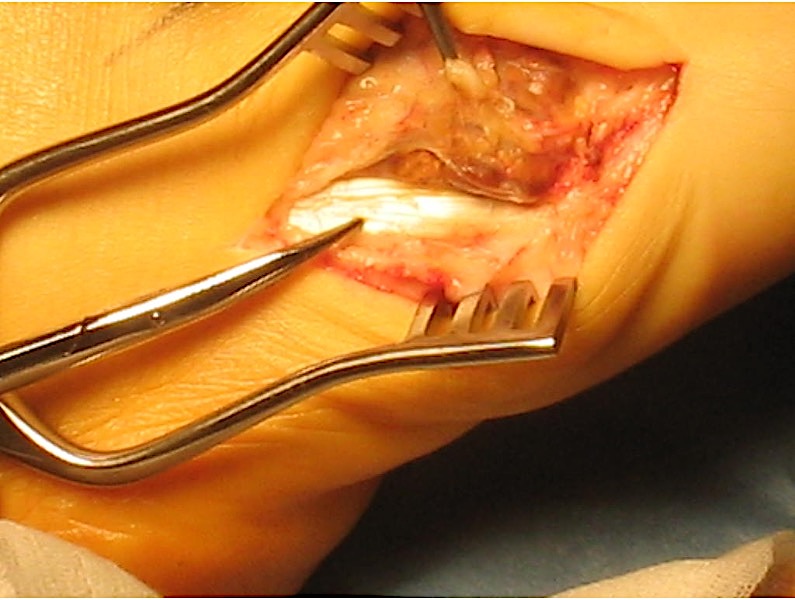

GCT flexor tendon sheath

GCT of tibialis posterior tendon sheath

- local excision

- surgical excision of 20 giant cell tumour tendon sheath foot & ankle

- recurrence rate 20%